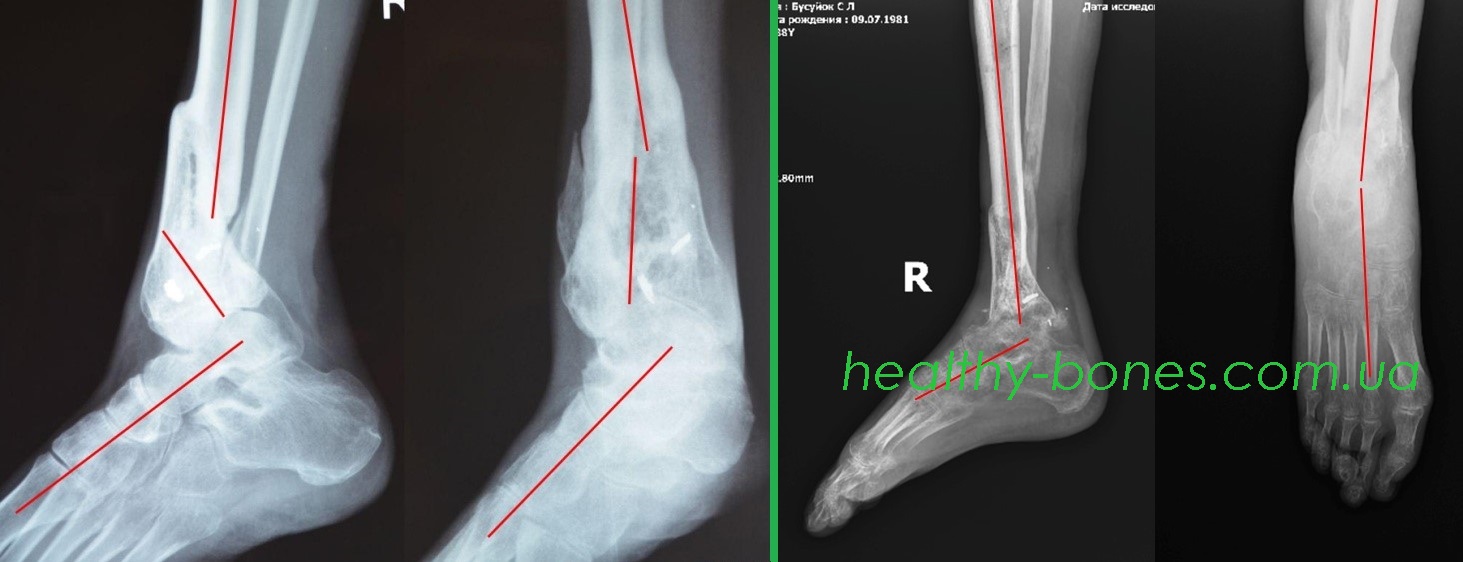

В результате боевых действий на Донбассе получил осколочное ранение голени с многооскольчатым переломом дистальной трети правой большеберцовой кости и надлодыжечным перелом малоберцовой кости. Лечился в военном госпитале. Переломы срослись с укорочением и сложными угловыми и ротационной деформацией. Сергею сказали, что сделали все, что могли и порекомендовали приспосабливаться к той ноге, которая у него есть, в противном случае надо будет делать ампутацию и ходить на протезе. В течение года Сергей безуспешно старался начать ходить, обращался в разные медучреждения и везде ему предлагали ампутацию.

По рекомендации волонтеров обратился к нам за помощью. Нами были проведены этапные операции, направленные на устранение всех видов деформации и укорочения конечности. Через 2 года после начала лечения Сергей смог полноценно пользоваться своей правой ногой.